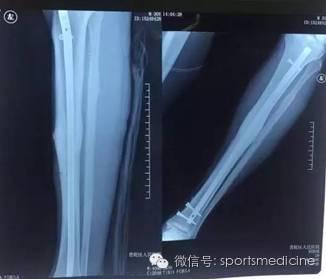

运动医学戈大夫告诉大家,其实这里面包含多方面因素。首先手术使用了骨折中常用的ORIF也就是切开复位内固定,并选择了可靠的髓内钉技术,其实也就是在胫骨(小腿骨)中插入了一根钢钉做为支撑,以避免骨折发生移位。再有登巴巴本次的骨折也恰好没有发生很严重的骨折移位和开放伤。虽然运动员身体素质和恢复能力的确强过不少普通人,但是骨折和伤口软组织愈合也必须遵循普通人类的规则,2周才差不多可以拆线,也才能碰水。这是水下训练的前提条件。解释到这里似乎也没有什么特别不是嘛!

或许还有人疑问,这么快可以骑自行车训练了?我告诉大家是完全可以的,之前我介绍了ORIF骨折复位内固定,其实这个手术的出现就是为了帮助患者更快的恢复,要不然骨折不移位完全打个石膏就行啦,何苦要手术呢?只是我们国内传统的思想总认为手术后要静养,不能多动,这样很多人术后起码一躺就一个月。一个月后骨折是固定牢靠了,肌肉同时却也萎缩了。所以早期开始康复是快速恢复功能的最重要的因素,只要手术固定确实,完全就可以很早开始下地康复训练,而且一定负荷的机械刺激,对于骨折端的愈合反而是有好处的,可以促使愈合。康复慢不单单是病人方的普遍认识不足,更是我们骨科医生对于术后康复的不够重视。

为什么很多国内骨科医生都觉得登巴巴的手术不是很复杂?其实的确如此。我们国内的骨科医生做过复杂的胫腓骨骨折手术绝对不会比登巴巴的主刀医生少。但是国内对于术后康复的重视,和功能迅速恢复的意识普遍薄弱,而且骨科医生通常没有时间去跟进和关注术后康复,孰不知康复在运动损伤术后的恢复中可以说占一半的功劳。目前其实并没有看到卡塔尔那边给登巴巴很特别很先进的康复设备,事实上术后早期也不需要,关键是治疗的理念和康复的意识,这才是登巴巴可以这么快下地的神奇之处。